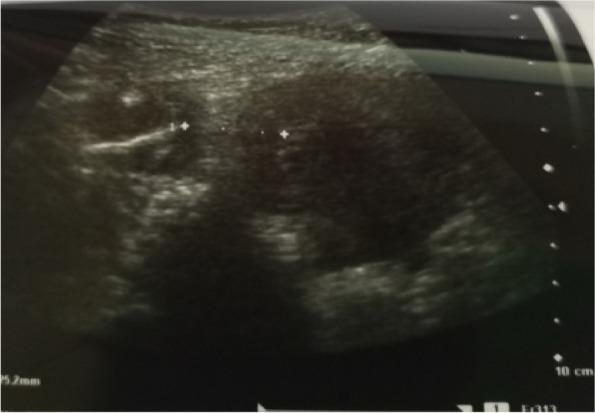

Loss of Intra Uterine Device (IUD) following silent perforation of the uterus either during or after IUD insertion is an uncommon finding due to a lack of immediate follow-up. We report a rare case in which uterine perforation following the migration of IUD to the right fallopian tube without visceral injury. The patient presented with lower abdominal pain and pain during sex for one year since IUD insertion. On examination, we noted tenderness on the right suprapubic region and on speculum examination, no IUD thread was seen. A radiological pelvic examination showed an empty uterus without an IUD. Laparotomy and retrieval of migrated IUD was done followed by repair of perforated uterus.

宫内节育器(IUD)在插入过程中或插入后因子宫隐性穿孔而丢失,由于缺乏即时随访,这种情况并不常见。我们报告一例罕见病例,宫内节育器迁移至右侧输卵管后发生子宫穿孔,但无内脏损伤。该患者自放置宫内节育器后出现下腹部疼痛和性交痛一年。检查时,我们发现耻骨上区右侧有压痛,阴道窥器检查未见宫内节育器尾丝。盆腔放射学检查显示子宫内无宫内节育器。进行了剖腹手术并取出迁移的宫内节育器,随后修复穿孔的子宫。